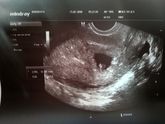

Сходила на УЗИ

25 июля 2018 17:40

Уже немного видно маленького, есть сердцебиение, всё хорошо. Я такая счастливая!). Врач сказала, всё соответствует срокам, ЧСС 174. Всем планирующим желаю испытать это чувство эйфории!)